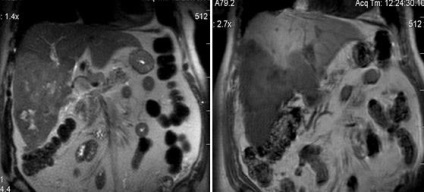

Natív és postkontrastnye MR hemangioma diffúz típusú amplifikációs.

Lobularis hiperplázia a máj (UCP)

A második frekvencia jóindulatú májtumor. Ez magában foglalja a májsejtekben, Kupffer sejtek és epevezeték. A központi része van egy heg, azaz septum - septum. Sokkal gyakoribb felnőtt nők. A tünetmentes és gyakran kimutatható véletlenül. Nem maligniziruetsya, és általában nem okoz egészségügyi problémákat (rendkívül ritka vérzés).

MRI az UCP natív és dinamikus kontrasztos tanulmány. MRI dinamikus kontrasztanyagos megbízhatóan érzékeli, és lehetővé teszi egyedi képződése jellemzi a máj, mint a csomóponti noduláris hiperplázia.

Noduláris hiperplázia Máj